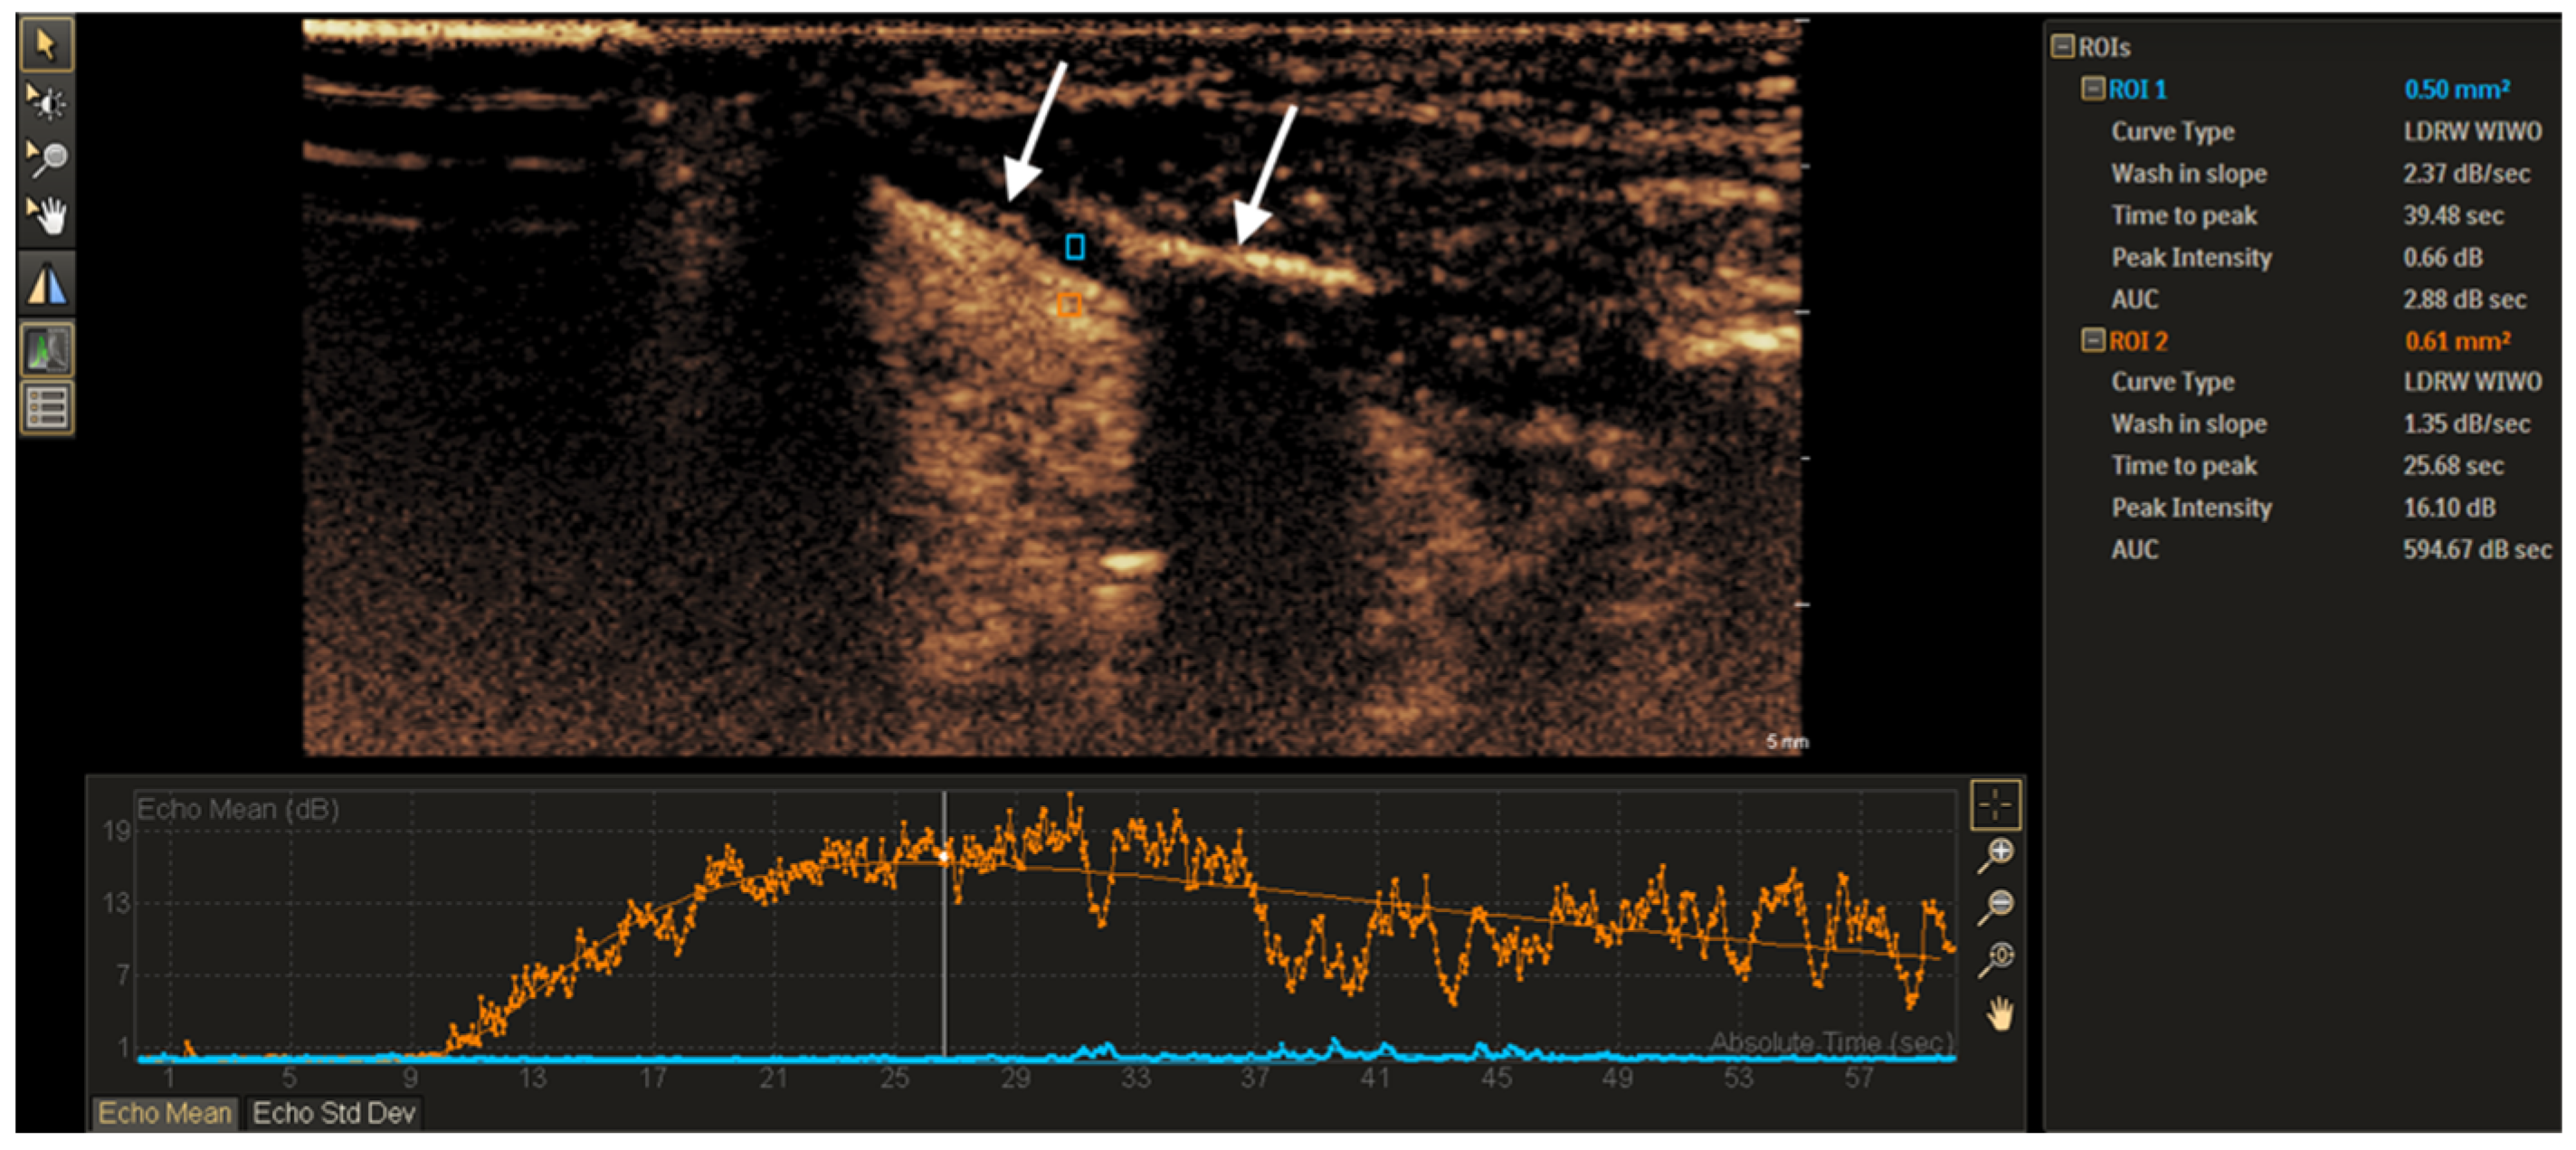

3.1. CEUS Imaging Features of Non-Ossified Thyroid Cartilage

3.2. TIC Analysis of Non-Ossified Thyroid Cartilage and Tumor Tissue